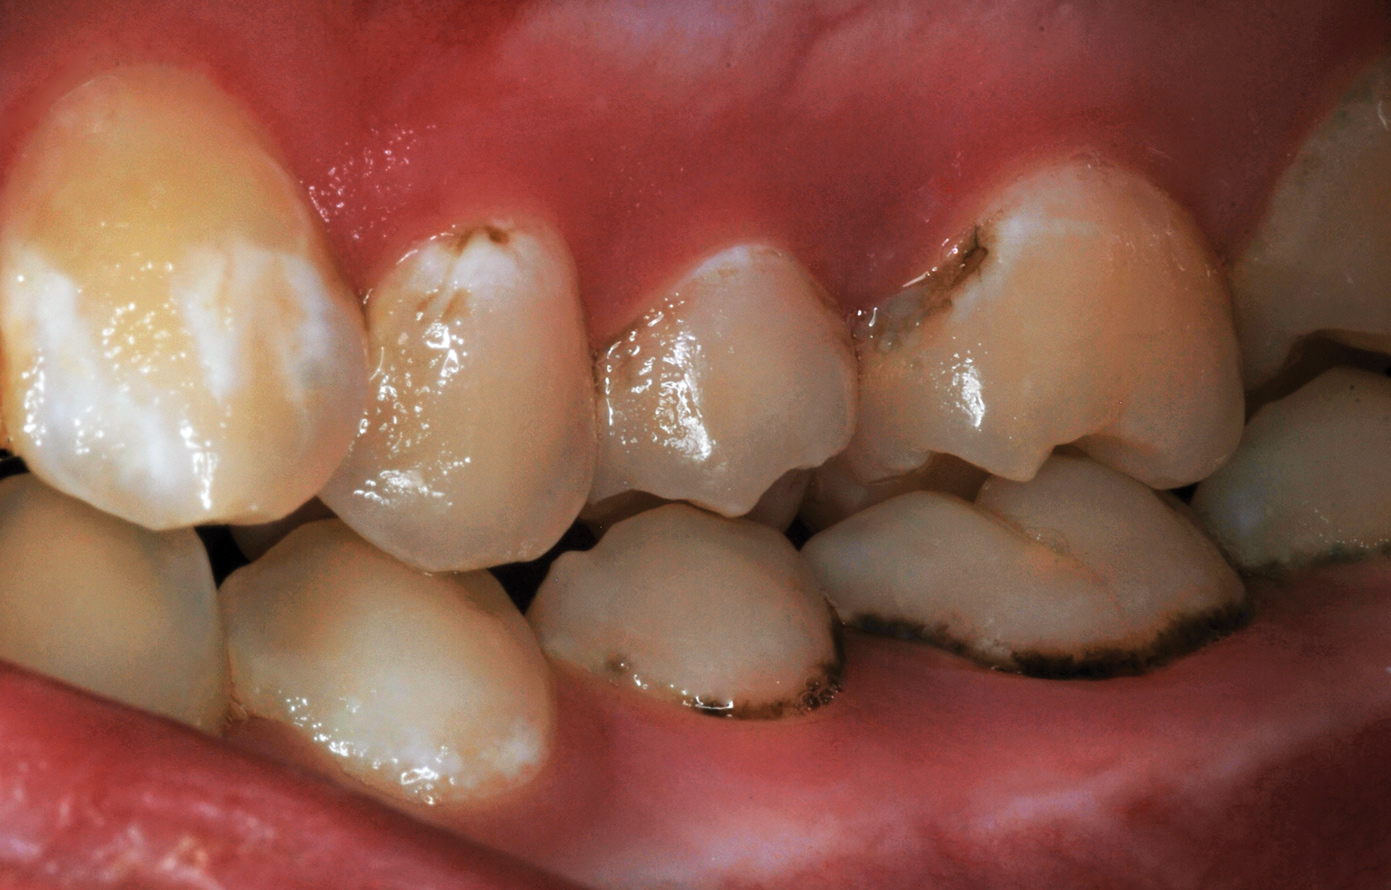

Fig 8. Caries prevention with SDF is critical on distal surfaces of primary second molars to avoid caries infection on mesial surfaces of permanent first molars. Note the Class 2 restorations in both primary molars in this 9-year-old patient whose first molar needed occlusal resin-based composite restoration.

Figure 8